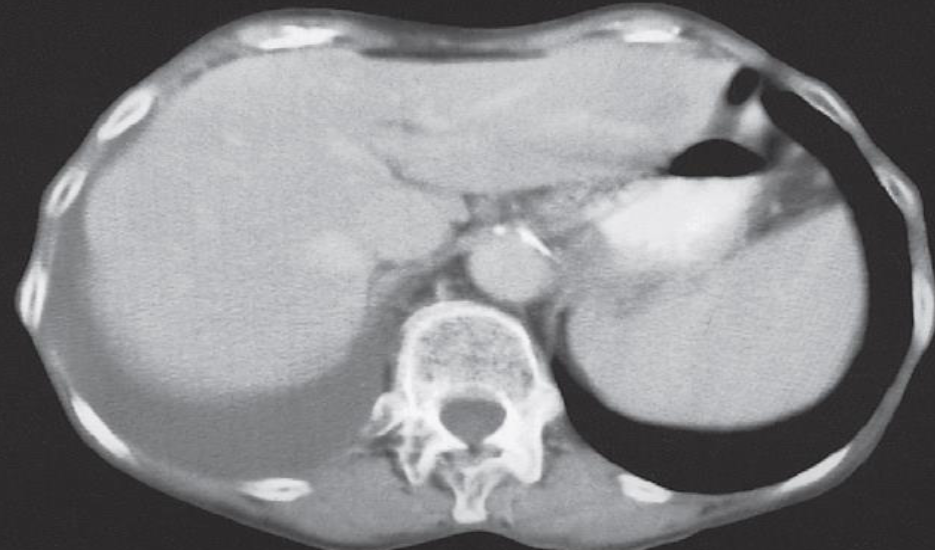

The patient had carcinoma of the bronchus.

CT scan of liver metastases. There are a large number of low density lesions in both lobes of the liver, which show enhancement around their edges.

LIVER METASTASIS

Imaging examination CT scan